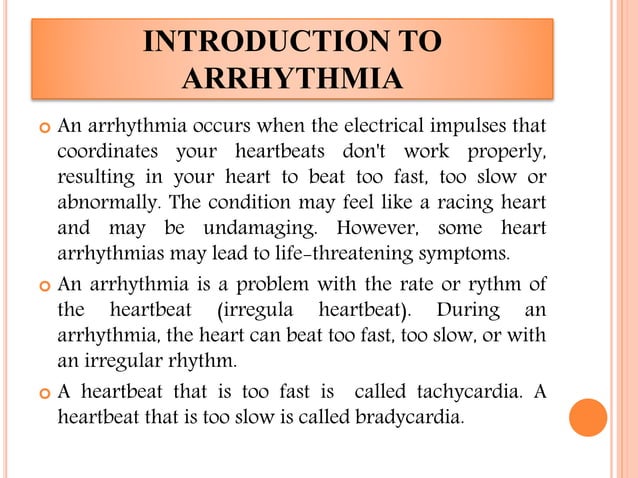

Arrhythmia : Causes, Symptoms And Treatment

www.slideshare.netArrhythmia : Causes, Symptoms and Treatment

www.slideshare.netArrhythmia : Causes, Symptoms and Treatment

Arrhythmia : Causes, Symptoms And Treatment | PPTX

www.slideshare.netArrhythmia : Causes, Symptoms and Treatment | PPTX

www.slideshare.netArrhythmia : Causes, Symptoms and Treatment | PPTX